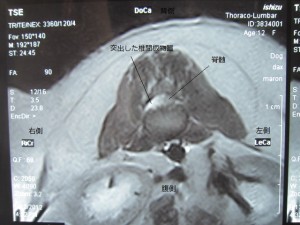

M・ダックス ♀ 12歳 7.2kg

両後肢麻痺で来院。深部痛覚もほぼなくなっていた。尿もでないということで、CT・MRIを実施した。

L1-L2の椎間板ヘルニアが見つかり、右側より片側椎弓切除術を行った。

術前のMRIです。場所は腰椎の1-2番目の間です。

白い部分が圧迫部位になります。

右側から大量に突出しているのがわかります。

※別病院にて撮影